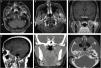

Transpatial skull base lesions involving the infratemporal fossa (ITF) are challenging due to the complex neurovascular structures of the region. Open approaches have traditionally been utilized to access these spaces. We present a 55-year-old woman presented with a mesenchymal mass involving the left ITF and masticator space. A combined endoscopic endonasal transpterygoid approach was performed followed by an endoscopic transoral-transmandibular corridor to access and resect the tumor. The post-operative course was unremarkable with no recurrence during her follow-up. Combined endoscopic approaches for transpatial tumor resection offered sufficient exposure to access safely each space.